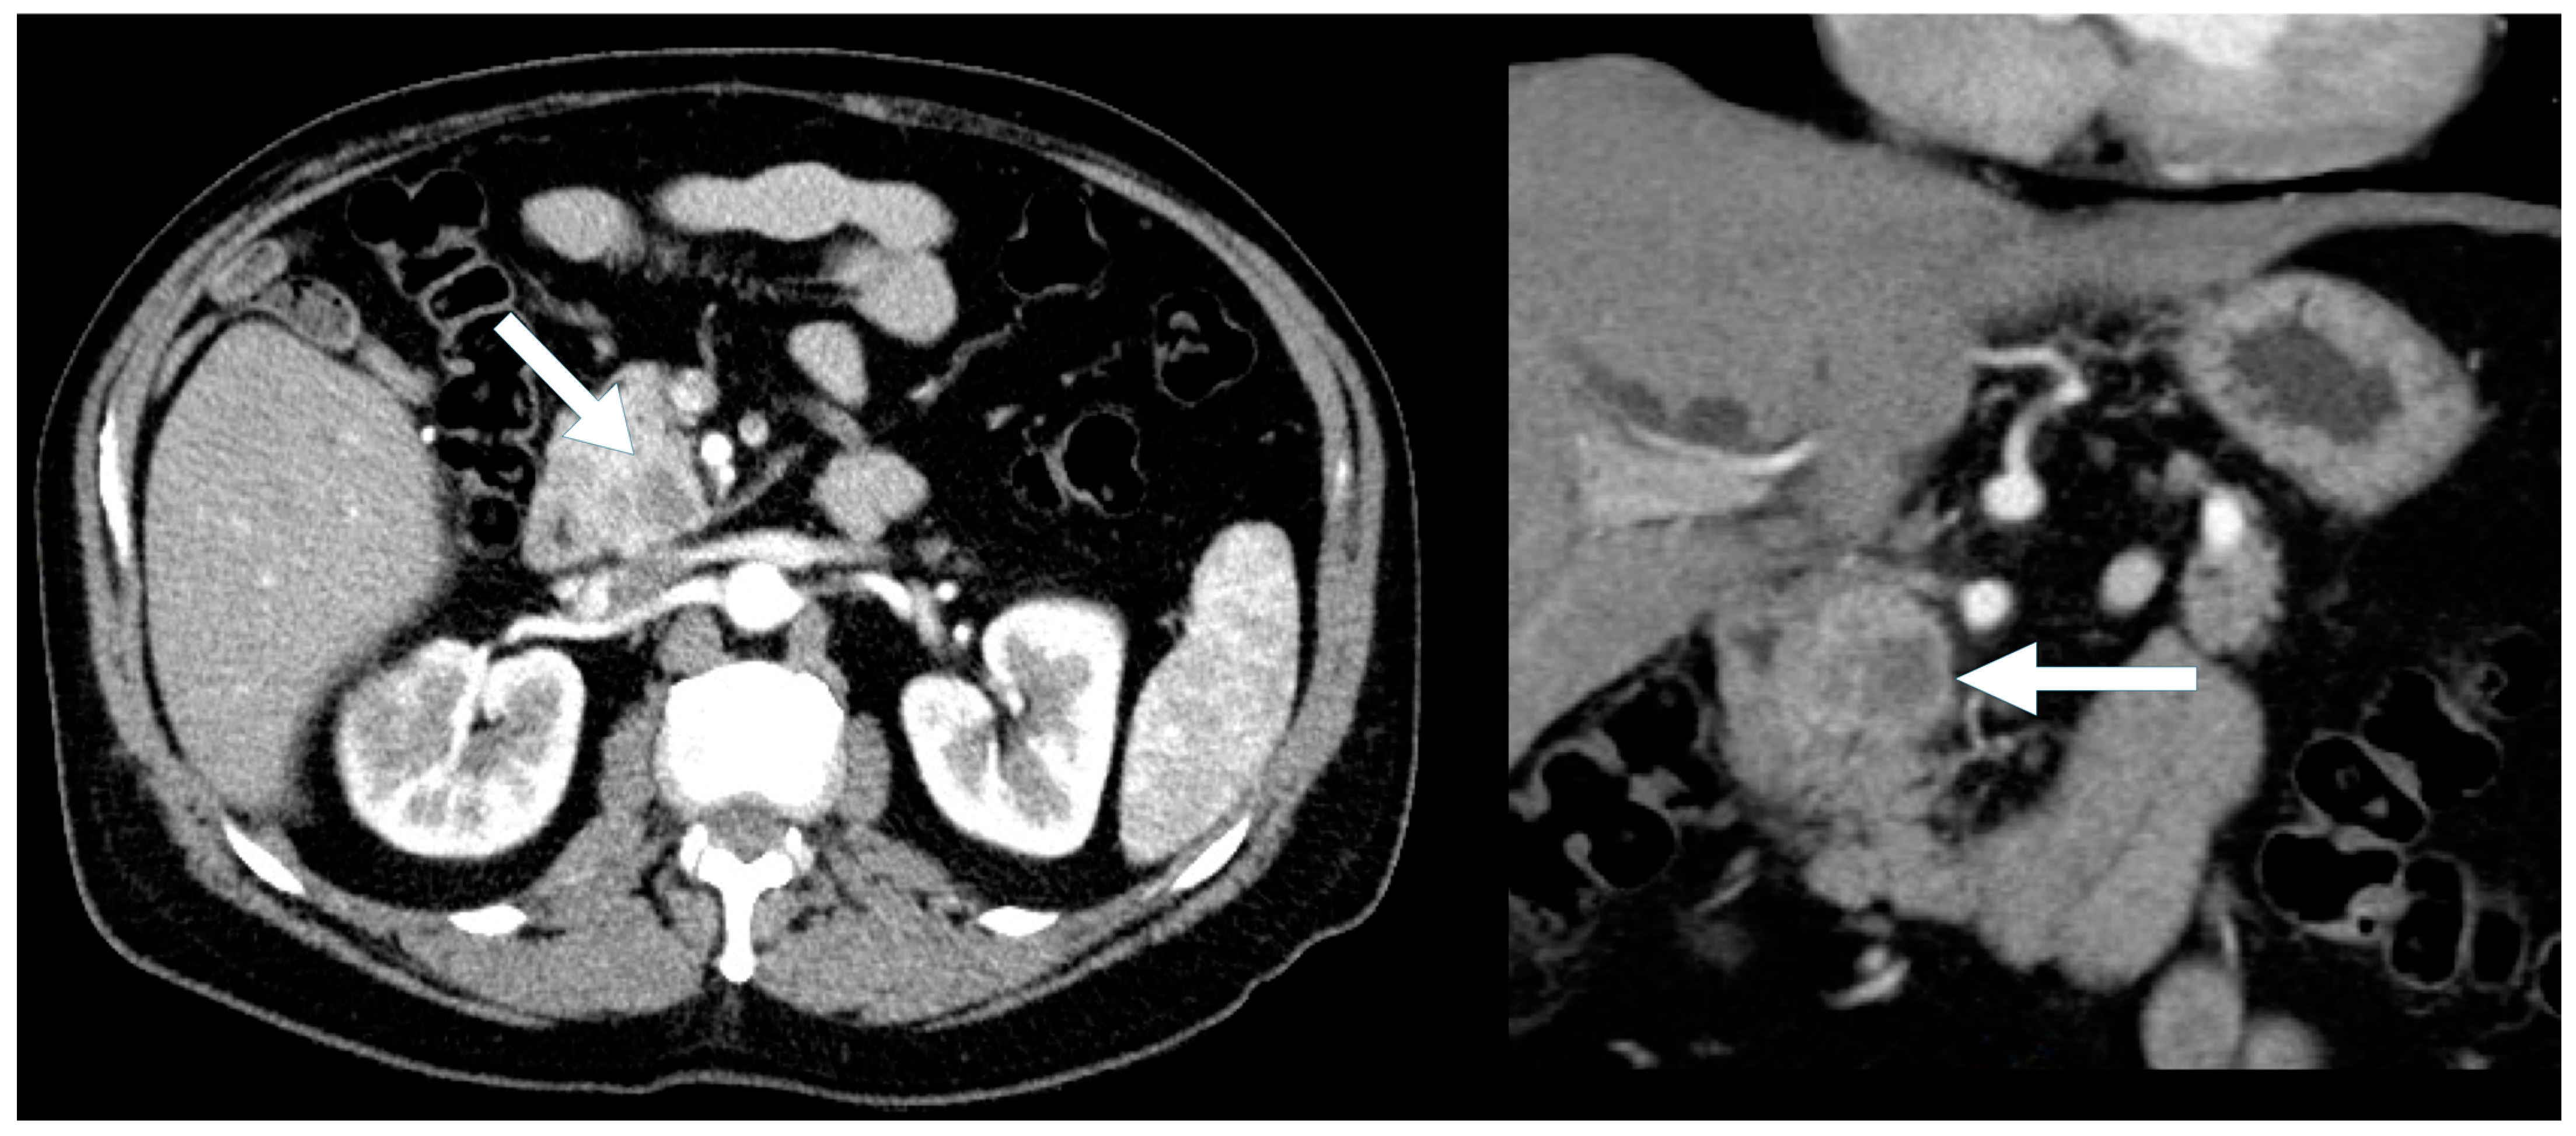

Most cases of hypoenhancing PNENs (n = 11) presented symptomatically (64%), and the lesions were significantly larger (median size 4.8 cm vs. 1.7 cm for typical PNENs). Calcifications were observed in 9% of hypoenhancing PNENs. As pointed out, these tumors were significantly more likely to present with advanced disease compared to other PNEN subtypes (Fisher’s exact test, p = 0.016) (Figure 6 and Figure 7).

Figure 6. A 47-year-old male presenting with biliary obstruction. CT (left): Arterial phase imaging shows a 2.5 cm hypodense mass in the pancreatic head (arrow). PET-CT (right): Performed after ERCP and biliary stent placement, demonstrating an intensely FDG-avid pancreatic head mass (arrow), consistent with a poorly differentiated primary neuroendocrine tumor. Metastatic disease involving porta hepatis and peripancreatic lymph nodes, as well as liver metastases, is also evident on the PET.